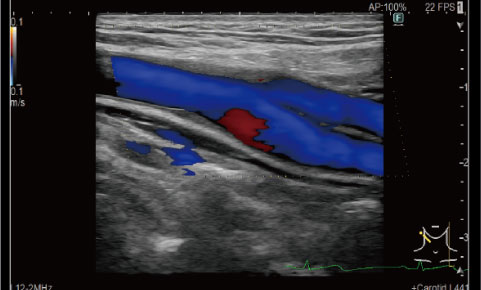

カラードップラー機能で

血流の状態を「見える化」カラードップラー超音波検査は、血流速度と方向を解析し、血液の流れを色で映し出すことができます。これにより、血管のつまりや狭さ、心臓や臓器の血流の状態まで詳しく確認でき、病気の早期発見や正確な診断につながります。